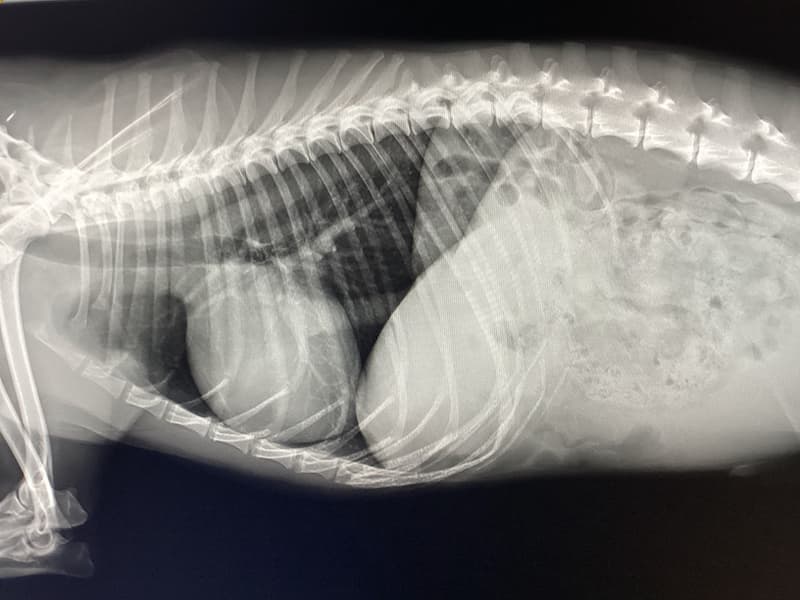

ストラバイト尿石症とは尿中のミネラル成分が結晶化し、ストラバイト結石となって膀胱や尿道にできてしまう病気です。ストラバイト尿石症の症状には頻尿や血尿、トイレの失敗などが挙げられます。排尿時に痛みが見られたり陰部を仕切りに舐めると言った症状が見られることもあります。また、結石が尿道に詰まってしまい尿道閉塞を引き起こすと、命に関わる可能性のある危険な病気でもあります。結石が作られる原因として、食事や体質のほかに、膀胱内に感染した細菌によって尿のpH(酸性度)がアルカリ性に傾くことも原因とされています。ストラバイト結石は食事療法によって溶かすことのできる結石です。ただし結石が大きすぎる場合や食事療法に反応しない場合は外科手術が適応になることがあります。ストラバイト尿石症の診断には尿検査や膀胱のエコー検査が重要になります。お家のわんちゃん、ねこちゃんに上記の様な症状が見られる時はお早めに当院にご相談ください。